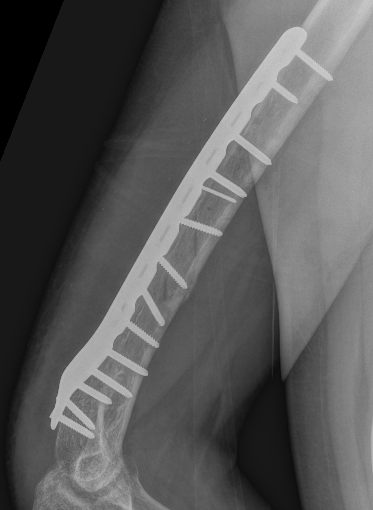

Open ORIF with plate

Plate

- narrow large fragment 4.5 mm DCP / long Philos proximal humeral plate

- minimum 6 cortices above and below

- can consider dual plate

Failure of fixation

- 4.5 mm plate with 6 cortices above and below

- if use 3.5 mm long proximal humeral plate, suggest 8 cortices below

- consider dual plating in proximal fractures with insufficient fixation, or in poor bone quality

Revision of fixation to longer posterior plate